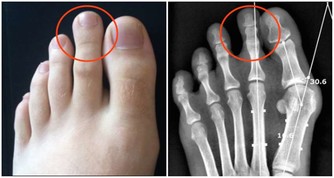

那就是膕窩囊腫的患者,膕窩囊腫泛指膕窩內的滑囊炎,

是因為膝關節積液,屈膝時腔內壓力增高,迫使滑液後移形成的一種疾病,

如果給予按摩刺激,不但不利於健康還會延誤治療。